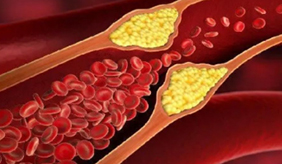

1、提前空腹12小时以上 血脂检查要求检查前空腹12个小时以上,具体来说就是前一天晚上吃过晚饭后不再进食,直到第二天早上空腹抽完血后再吃早饭。 如果没有......

查看更多>>

血脂晴雨表一次体检读懂身体信号血脂:生命的“隐形守护者”与“潜在威胁者”血脂,简而言之,就是血液中脂质的总称,主要包括胆固醇、甘油三酯以及磷脂等。它们虽不直接溶......

查看更多>>